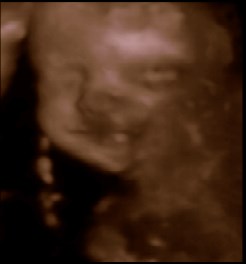

Se lige vores smukke datter

Det tog lidt tid, før hun ville vise os sit skønne ansigt, men hold da op, det var ventetiden værd!